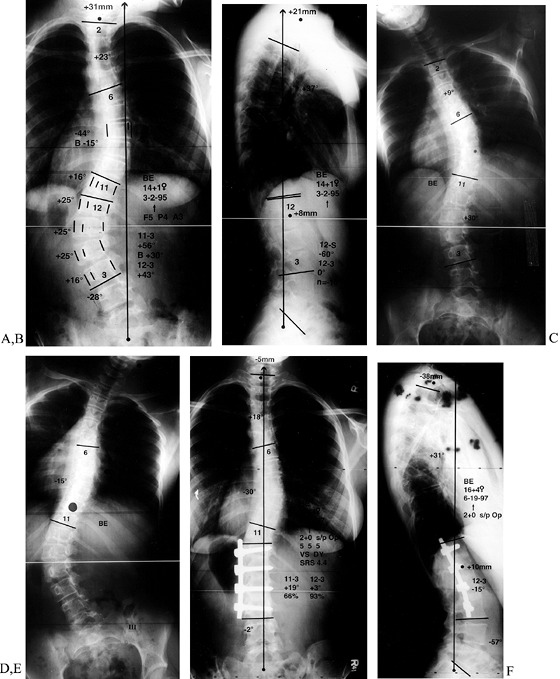

Close the wound over a chest tube as previously described. A sample case is illustrated in Fig. 155.25.

Figure 155.25. This 14-year-old girl has left thoracolumbar major and right thoracic compensatory scoliosis. Standing frontal plane (A) and sagittal plane (B)

radiographs show imbalance to the left in the coronal plane, and in the

sagittal plane flattening of the upper lumbar spine. On the left bend

x-ray, there is not a clear opening of the disc space above the lower

Cobb (C). On the right bend (D), the upper scoliosis corrects from 44° to 15°. Two-year postoperative radiographs (E,F)show

restoration of coronal balance and a well-healed fusion with normal

sagittal plane alignment. The standing postoperative posteroanterior

radiograph (E) shows instrumentation from

T12 to L3, the upper end vertebra level having been left out to allow

for compensation. The sagittal plane angulation has been restored (F).